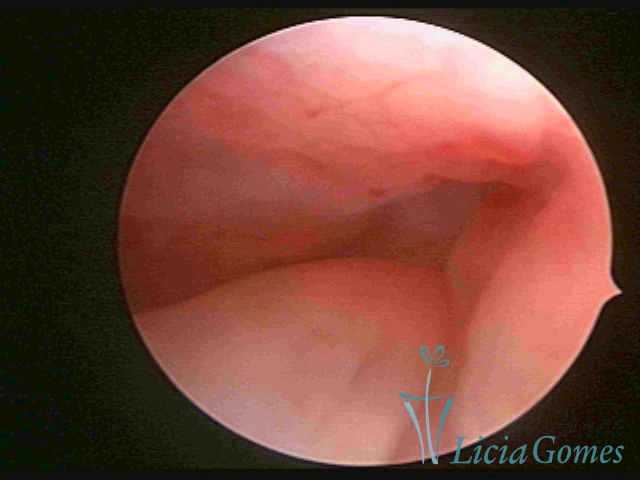

ENDOCERVICAL POLYPS

Benign tumors resulting from the reactive focal proliferation to inflammatory processes or hyperestrogenism situations, which may be sessile (with a large implantation) or stalked.